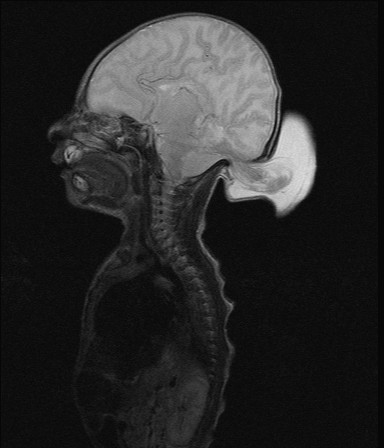

Encephaloceles

Encephaloceles are often grotesque-looking congenital swellings arising from the head or face, that may make childbirth difficult. Child often appears to have a swelling as large as the head. Most of these swellings can be surgically removed successfully.